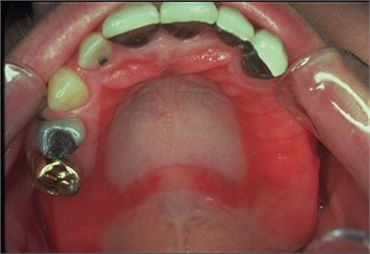

Denture stomatitis

Denture wearing also asks for proper maintenance. This includes regular cleaning of the denture and removing them at night. When the maintenance of the denture is not done properly, it leads to an inflammatory reaction in the arch that bears the denture. This is called stomatitis. Stoma means the mouth and -itis indicates inflammation. Since this condition is triggered by factors associated with denture, it is called denture stomatitis. It is also called denture sore, chronic atrophic candidiasis or denture-associated erythematous. This condition was first described in 1962.

Denture stomatitis leads to reddish appearance of the areas that bear the denture. There can also be pinpoint reddish areas in the affected region. The soreness is triggered due to infection caused by a species of microbes called Candida. These microorganisms thrive best in the acidic environment. When dentures are unclean, do not fit properly, then the area covered by the denture does not receive saliva. Saliva has a protective role, as its flushing mechanism keeps the mouth clean. When the saliva does not reach the area, then the region below the denture becomes more acidic. This allows Candida and other microbes to predominate, causing soreness.

The inflammation can at times spread to the corner of the mouth, leading to angular cheilitis (inflammation of the corner of the mouth near the lips). Denture stomatitis is more often seen in the region of upper denture compared to lower denture. This condition can also occur due to the components of the denture, that can be made of acrylic, cobalt or chromium. Moreover, denture stomatitis can be facilitated by underlying conditions like xerostomia (dry mouth), diabetes, HIV, etc.